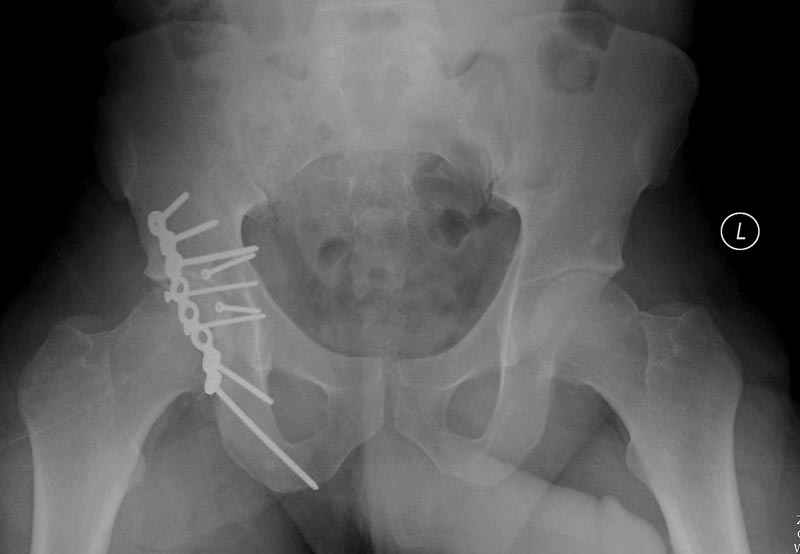

7:30 начало операции, больной на спине, попытка репозиции после анестезии N3, укладка больного на боку, доступ Kocher- Langenbeck, состояние седалищнего нерва около 2.5см кровоподтек, через joistick головка бедра приподнята, освобовождение сустава, фрагмент заднего края более 3х4 см репонирован на свое место. После промывания

сустава, репозиция вывиха (N4), фиксация фрагмента 2.7(4) мм шурупами и допольнительно реконструктивной пластиной на 8 дырок, фиксация 3.5мм шурупами проксимально и дистально.

Интраоперционные N5 косая запирательная и N6 подвздошный снимок